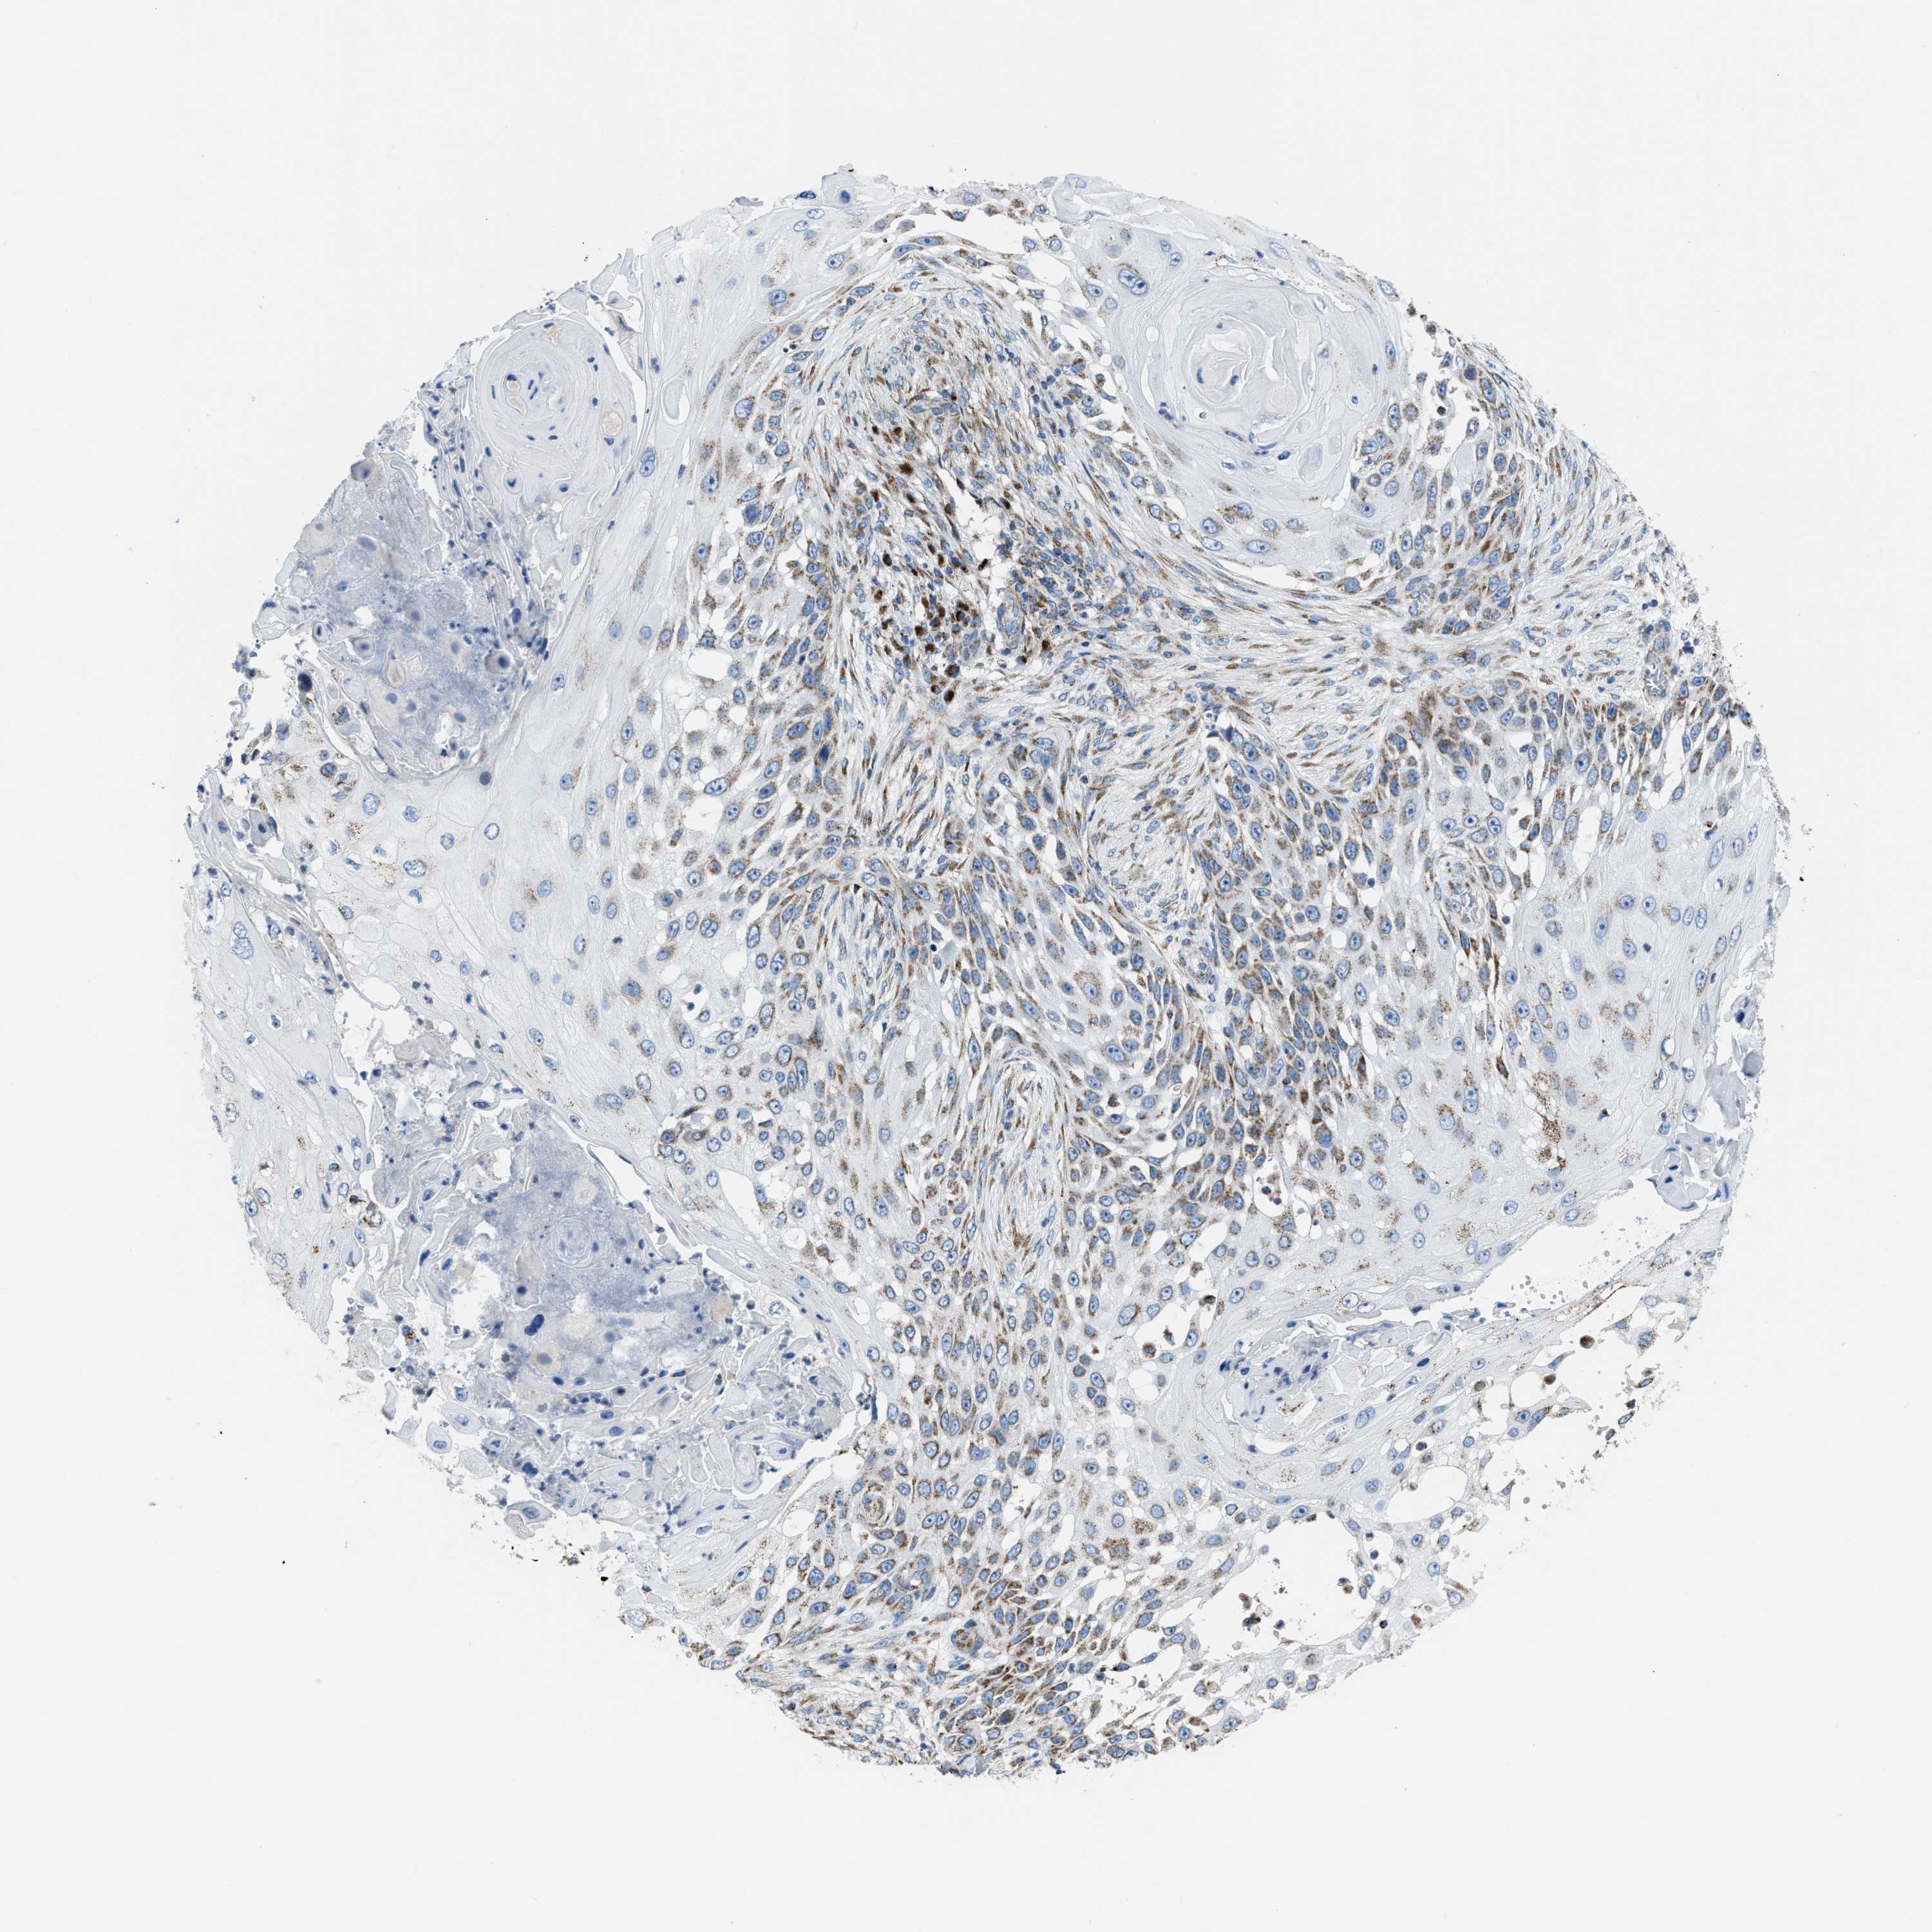

CANCER SKIN CANCER Show tissue menu

Basal cell and squamous cell cancer

SKIN CANCER - Protein expressioni

A mouse-over function shows sample information and annotation data. Click on an image to view it in a full screen mode. Samples can be filtered based on level of antibody staining by selecting one or several of the following categories: high, medium, low and not detected. The assay and annotation is described here.

Each image is clickable and will lead to virtual microscopy that enables deeper exploration of all samples and also displays staining intensity scores, fraction scores and subcellular localization as well as patient and tissue information for each sample.

Antibody HPA018921

Basal cell carcinoma

Squamous cell carcinoma, NOS

Squamous cell carcinoma, metastatic, NOS